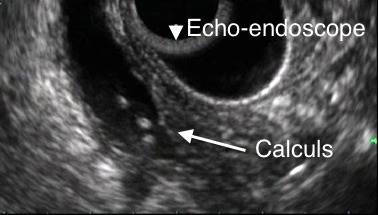

Deux examens sont performants pour mettre en évidence une lithiase de la voie biliaire principale avec une sensibilité supérieure à 90 % : la cholangio-IRM et l’écho-endoscopie. L'écho-endoscopie sera réalisé en urgence chez un malade dans le but de bien visualiser le calculs qui obstrue le cholédoque et surtout pour réaliser dans le même temps anesthésique une extraction du calcul par la réalisation d'une sphinctérotomie endoscopique par (CPRE)

L’écho-endoscopie est un examen endoscopique, nécessitant une anesthésie générale qui permet une visualisation directe par échographie (ultrasons) des parois et du contenu de la voie biliaire principale (Cholédoque) et des organes adjacents. comme la tête du pancréas. L’examen s’effectue à l’aide d’un endoscope souple qui est doté d’une caméra et d’une sonde d’échographie à son extrémité. Cet instrument est introduit par la bouche et ensuite guidé sous contrôle visuel jusqu’à proximité de la paroi duodénale proche de l'ampoule de Water. Cet examen présente une sensibilité de 84 à 100 % et une spécificité de 96 à 100 % et une VPP de 95 à 100 %. En cas de visualisation de calculs de la VBP, une sphinctérotomie endoscopique (CPRE) peut-être réalisée pendant la même anesthésie pour évacuer le calcul.

Figure n°1 : Echo-endoscopie

Figure n°2 : Echo-endoscopie

(Copyright SFED - Flèches Hepatoweb.com)